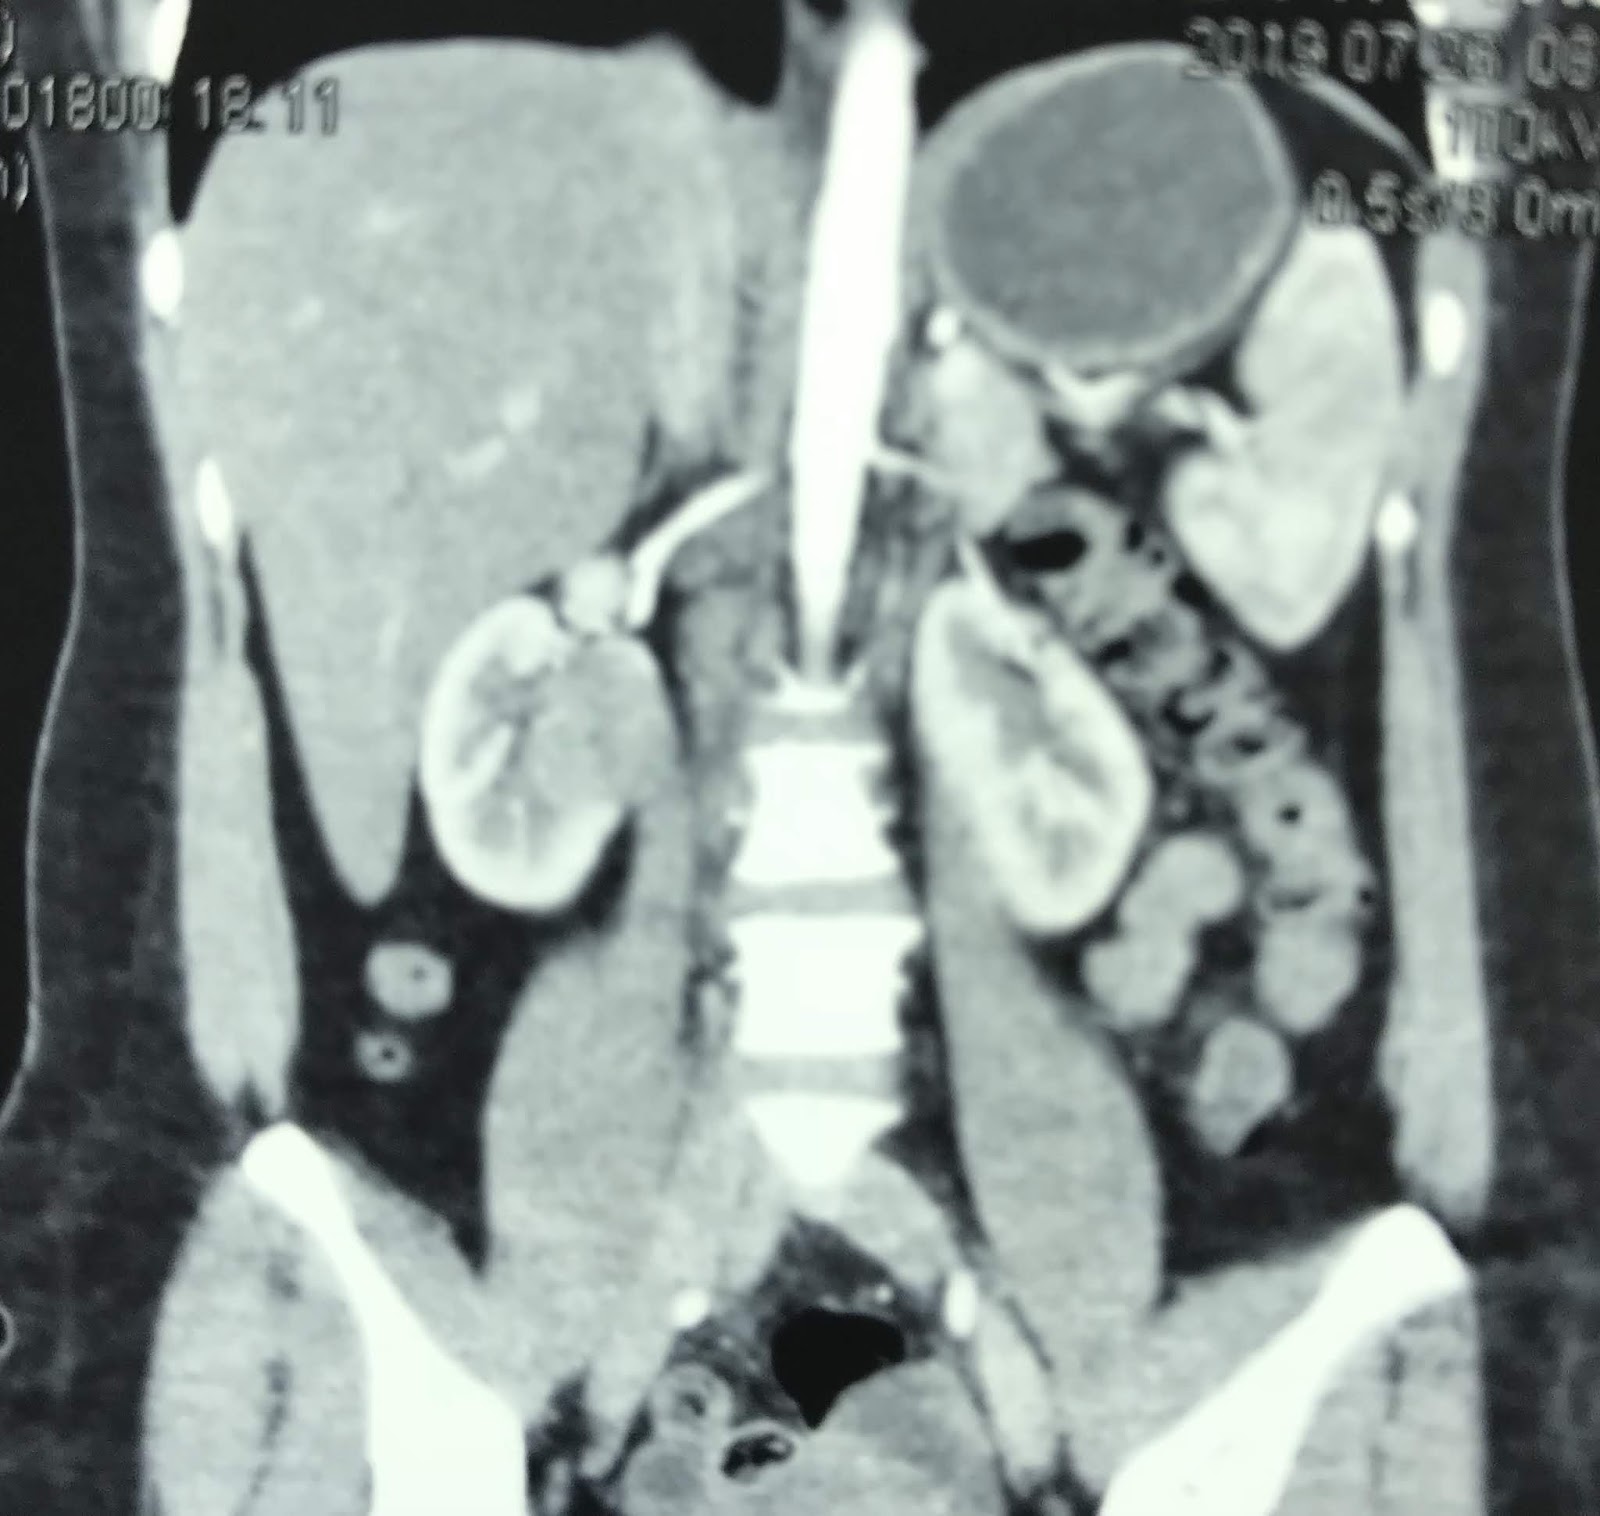

Initial preoperative CECT scan (coronal section) showing horseshoe Horseshoe Kidney Ct Images horseshoe kidney is a congenital anomaly characterised by the fusion of the poles of each kidney across. ct demonstrates the kidneys to be fused at their lower pole, located abnormally inferiorly immediately below the inferior mesenteric. the blood pool and delayed images demonstrate a renal fusion abnormality with the appearance of a. Axial computed tomography (ct) scan. Horseshoe Kidney Ct Images.